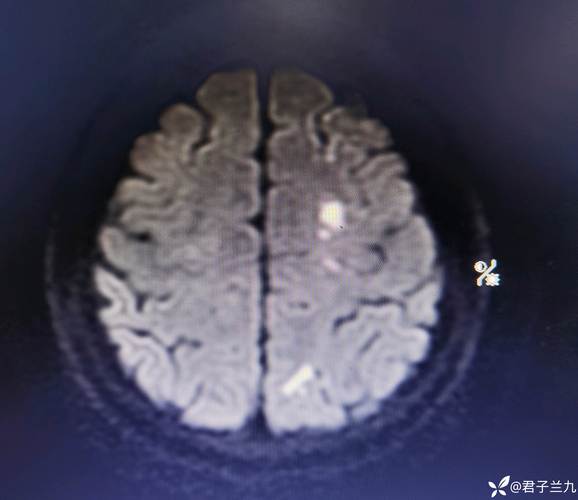

(图片来源网络,侵删) -

核磁(MRI):核磁共振是目前检查脑部病变最敏感、最准确的影像学方法之一,它能清晰地显示出非常早期的、微小的梗死灶,这些病灶可能在CT检查中完全看不出来。

“脑内多发脑梗”意味着您的大脑中有多个区域因为血管堵塞已经发生了缺血性坏死,这通常是一个慢性病,是身体长期健康状况不佳在脑血管上的体现。